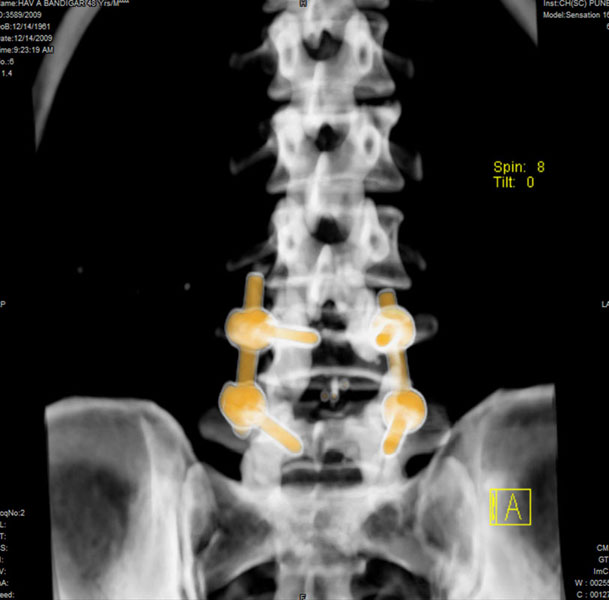

Spondylolisthesis malformations

Spondylolisthesis implies slippage of one lumbar vertebra over the next one, causing pain and nerve compression. Patient can also have difficulty in walking and numbness of the legs. Usually these patients need evaluation lumbar spine by MRI and CT scan, followed by spinal instrumentation and fusion.